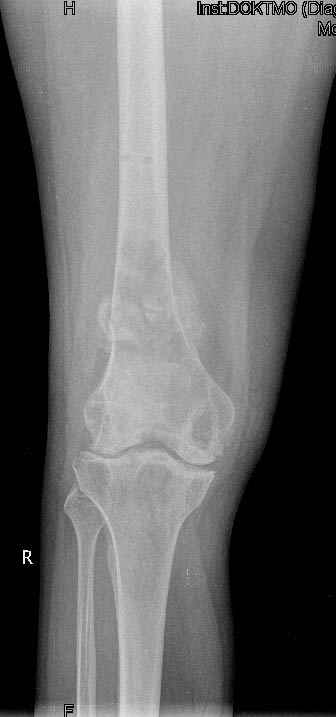

патологический перелом на фоне кистозных изменений

Коллеги! Окажите, пожалуйста, консультативную помощь. Мужчина, 41 год, 15 лет состоит на учете по поводу ревматоидного полиартрита, гормонзависимый (преднизолон получает нерегулярно). В процесс вовлечены крупные и мелкие суставы. 01.01.06 - без травмы наступил патологический перелом на границе н/3-с/3 бедра (перелом на фоне кистозных изменений?)

Биопсия из зоны перелома - <реактивные изменения в очаге перелома>, без признаков опухоли.

На рентгенограммах, помимо перелома, кистозные изменения на мыщелках б/берцовой кости и мыщелке бедра с другой стороны.

До травмы со стороный коленных суставов был болевой синдром, функция практически в полном объеме.

Какие будут предложения по тактика лечения перелома и кист на противоположом бедре?